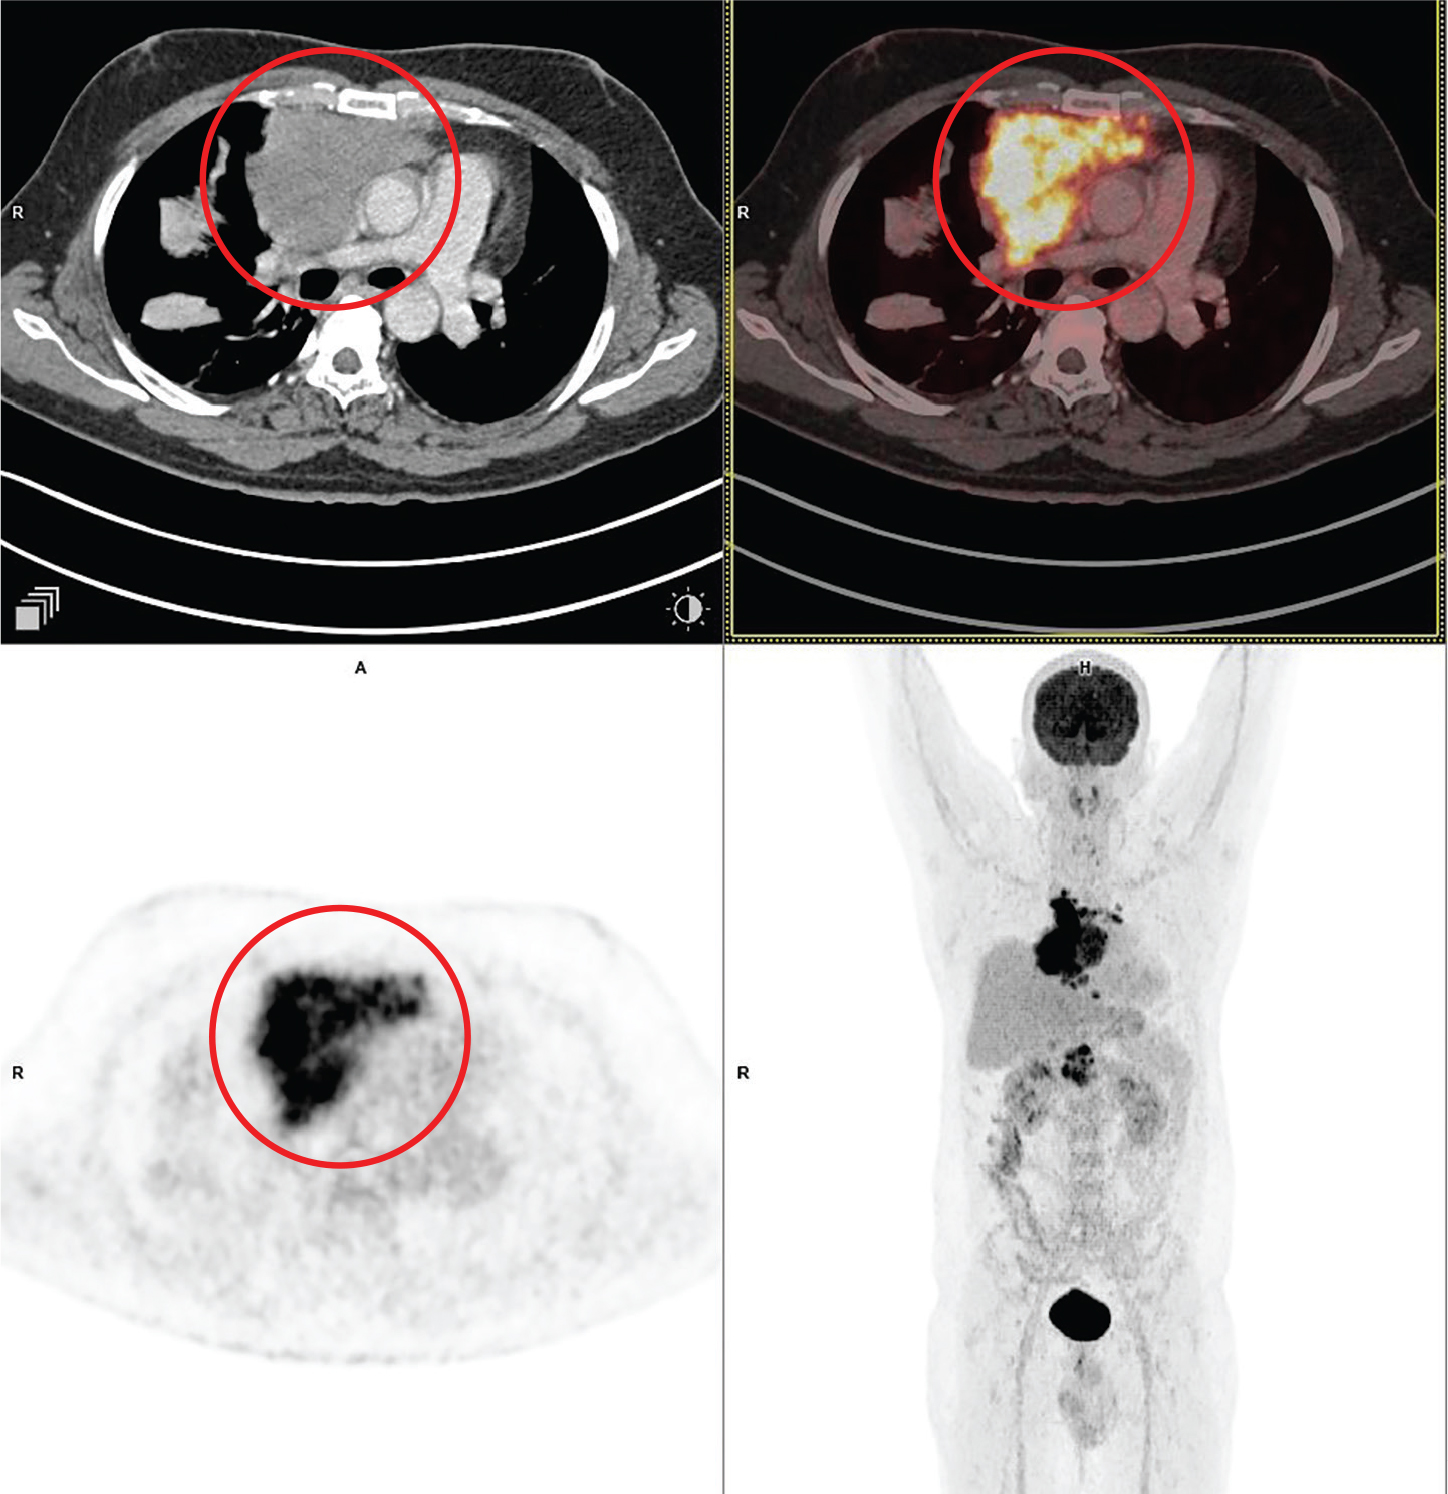

There are a few PET-based radiopharmaceuticals that are useful in workup of neurogenic tumors in the chest, in select situations. FDG, the most common radiopharmaceutical, has varying degrees of uptake in some of these neurogenic tumors. Although many of these tumors are benign, they are still metabolically active and can show increased FDG uptake. For example, schwannomas can show increased FDG uptake and are generally benign (69). In the absence of tissue diagnosis, they can be interpreted as false positives as malignant lesions based on their FDG avidity. Neuroblastomas also show increased FDG uptake, in primary and metastatic lesions, especially before treatment (70). However, post-treatment, uptake tends to be more variable. Generally, the uptake of FDG and MIBG tends to be concordant, however, MIBG may be superior in assessing treatment response, especially to assess residual disease. 18F-FDG PET/CT may be of value to assess non-MIBG avid neuroblastomas; however, more recently, Gallium 68 (68Ga) dotatate PET/CT is preferred for this (Figure 6). 18F-FDG PET/CT has also been shown to be useful in differentiating benign and malignant neurogenic tumors; however, SUV cut-off values have been variable, and other parameters like lesion to liver ratio have also been proposed as useful (7074). In our experience, the results are equivocal and differentiation between benign and malignant neurofibromas is not always feasible based only on 18F-FDG PET/CT imaging. Furthermore, benign and malignant neurofibroma lesions can coexist in the same patient and there may be a subsequent malignant transformation in some cases. FDG PET/MRI may also be beneficial for the evaluation of these lesions.

Fig 6

Figure 6. Posterior mediastinal mass that was pathologically confirmed as neuroblastoma. 68Ga - dotatate PET/CT images include axial CT (top left panel), fused axial PET/CT (top right panel), axial PET (bottom left panel), and maximum intensity projection (MIP) PET image (bottom right panel). In the red circle, a large lobulated heterogeneously 68Ga - dotatate avid and enhancing mass is seen involving the left chest cavity and posterior mediastinum with contiguous extension across the midline, and into the superior midline retroperitoneal / posterior abdominal cavity regions. There was additional 68 Ga - dotatate avid mass involving the paranasal sinuses, orbits, nasal cavity, facial bones and multiple other sites of skeletal involvement (not on the included PET/CT images and could be appreciated on the MIP image) that were suggestive of metastatic disease.